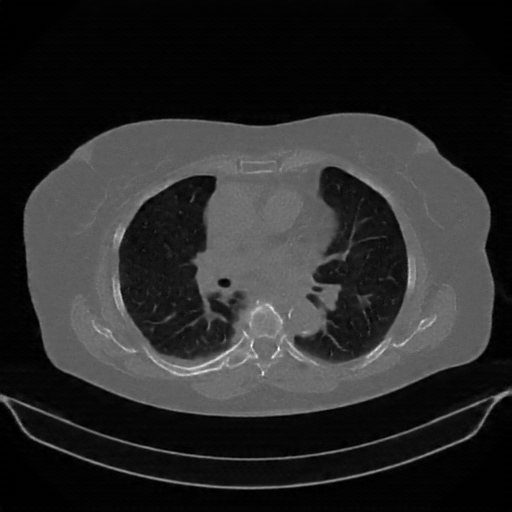

Original NATIVE CT scan (input)

Full window (WL 1023.5, WW 4095 β†’ Low βˆ’1024, High +3071)

Actual HU range: [-1024.0, 2210.0]

Lung window (WL -600, WW 1500 β†’ Low βˆ’1350, High +150)

Actual HU range: [-1024.0, 150.0]

Mediastinum window (WL 40, WW 400 β†’ Low βˆ’160, High +240)

Actual HU range: [-160.0, 240.0]